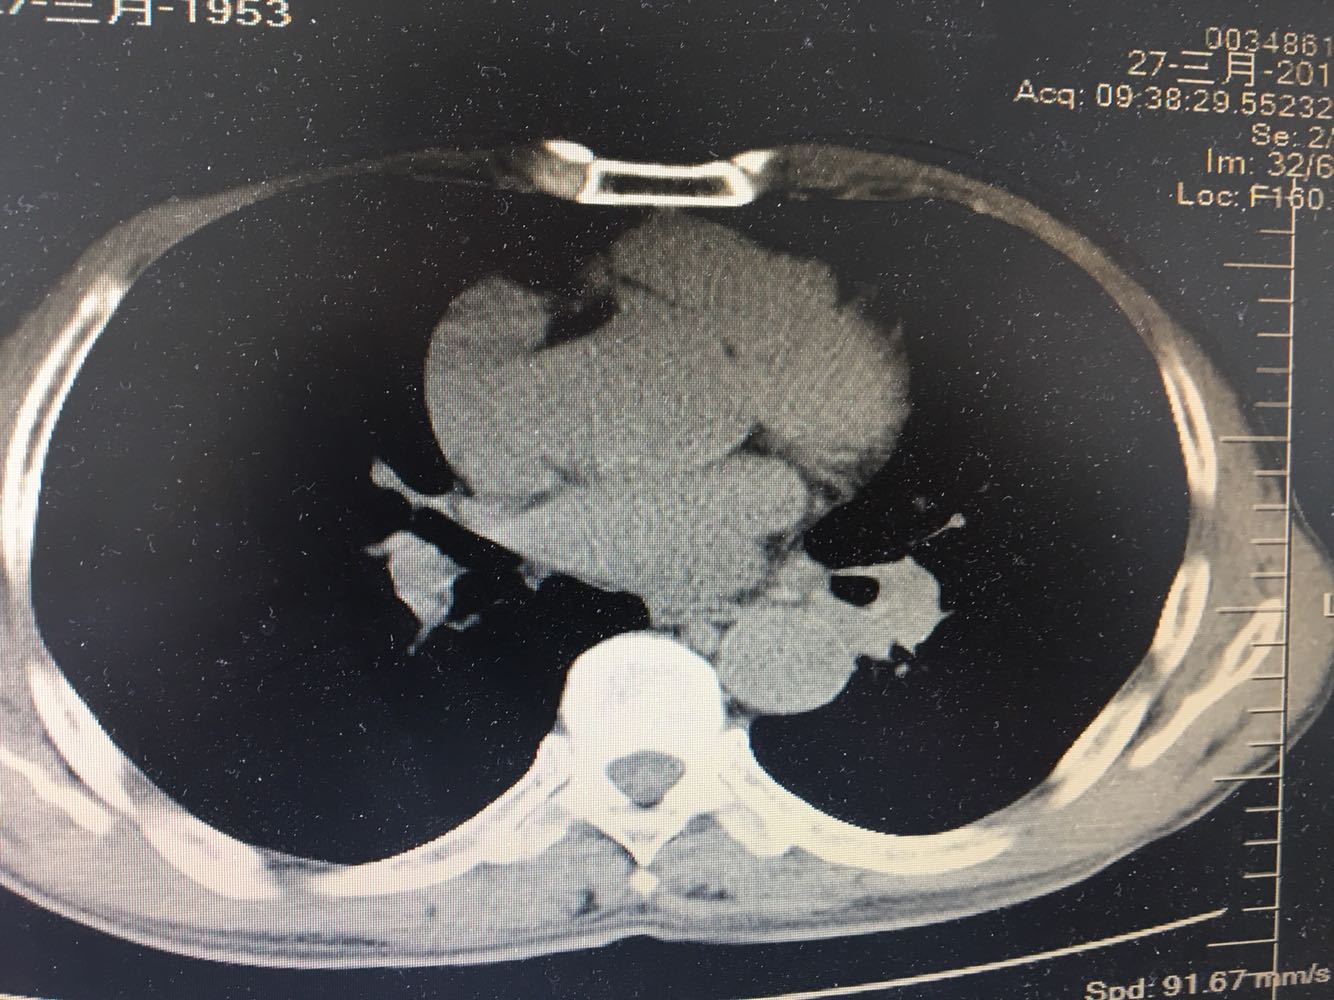

左肺下叶鳞癌

男,63岁,咳嗽1个月入院,患者自述1个月前无诱因咳嗽,阵发性干咳,无痰,时有血丝,无发热,左胸痛,活动后气短,静滴头孢13天无好转,门诊查肺CT后以 肺占位收入我科,病来饮食睡眠可,体重明显下降。既往疝气术后1年,吸烟史30年,每日1包。

左肺癌

左肺中央型肺癌,是否可以手术,还是化疗,放疗,靶向治疗?